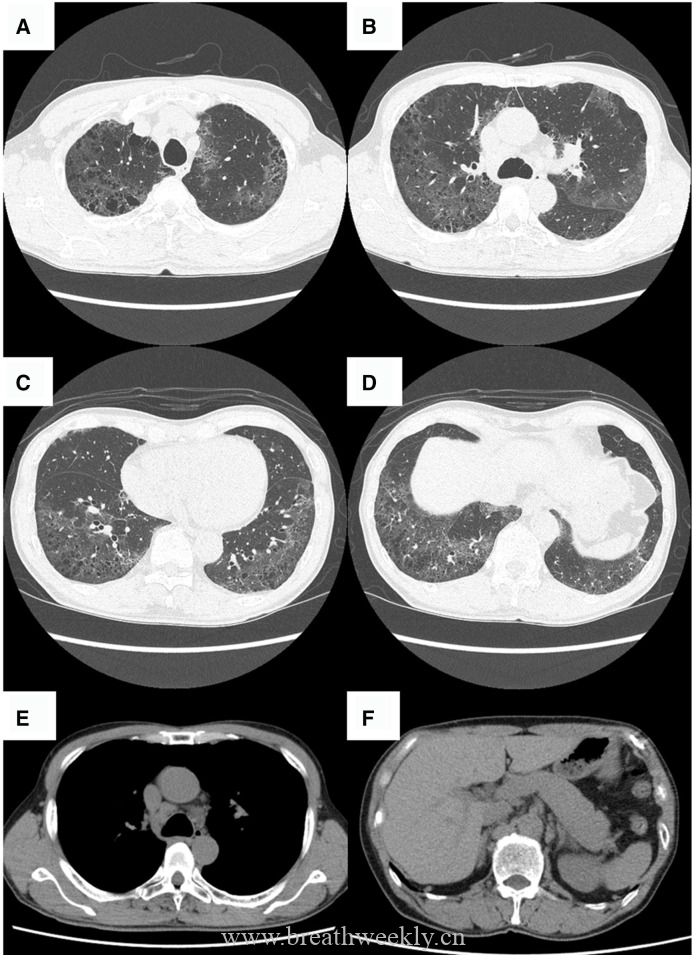

影像学检查

头颅CT除外颅内肿块及脑出血。脑及颈椎MRI(增强)除外CT隐性病灶,但发现右侧胸廓入口处囊性病灶。颈部超声及增强胸部CT:右侧上纵隔囊性占位,位于甲状腺右叶后下方,内见结节性实性成分及上极供血血管。胸部CT示前纵隔预期胸腺位置无异常软组织,提示胸腺脂肪萎缩。

⁹ᵐTc – 甲氧基异丁基异腈甲状旁腺显像:早期及延迟图像均可见甲状腺右叶下方异常摄取灶,摄取位于右上纵隔囊性病灶的实性成分内。

临床过程:因纵隔病灶位置位于甲状腺右叶后下方,术前考虑异位胸腺瘤或异位甲状旁腺腺瘤。CT及超声示无claw sign,排除甲状腺来源。99mTc-Sestamibi显像定位病灶。MG予糖皮质激素及IV免疫球蛋白治疗效果良好;高钙血症予IV补液及cinacalcet治疗。最终行机器人辅助纵隔甲状旁腺腺瘤及胸腺切除术,病理确诊甲状旁腺腺瘤。术后患者恢复良好。